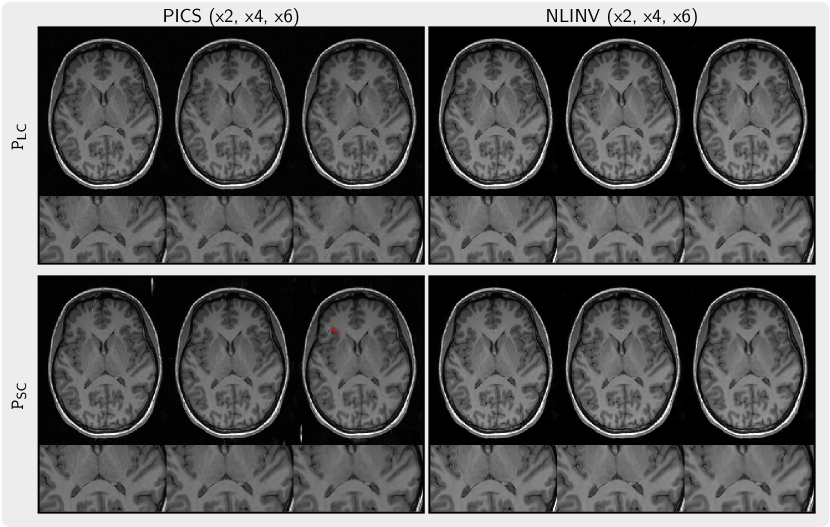

We performed the reconstruction using PSC and PLC. The k-space data were acquired from the brain of a healthy volunteer using MPRAGE sequence on 3T Siemens Skyra scanner (Siemens Healthineers, Erlangen, Germany) with 16-channel head coils. The protocol parameters were: TE = 2.45 ms, flip angle °, TI = 900 ms, and TR = 2000 ms, 4/5 partial parallel Fourier imaging, and 2-fold acceleration along one phase encoding direction. This acquired 3D volume has dimensions 256 256 224 and isotropic voxel size of 1 mm. We further undersampled the acquired 3D k-space data two and three times along two phase-encoding directions with the central region of size 30 25 reserved. The reconstruction was performed slice-by-slice in a 2D plane. To quantitatively assess the robustness of the priors, we computed PSNR and SSIM for the PLC-regularized reconstruction from 4 and 6-times undersampled k-space against the PLC-regularized reconstruction from 2-times undersampled k-space and compared it to PSNR and SSIM for the -wavelet regularization and the prior PSC.

Figure 6 presents the images regularized by the priors (PSC and PLC) trained on small and large datasets, respectively. When using PICS with the prior PSC artifacts become apparent in the background and in the brain, whereas no such artifacts are observed when applying the prior PLC. Furthermore, image details appear to be better preserved with high undersampling for the prior PLC.